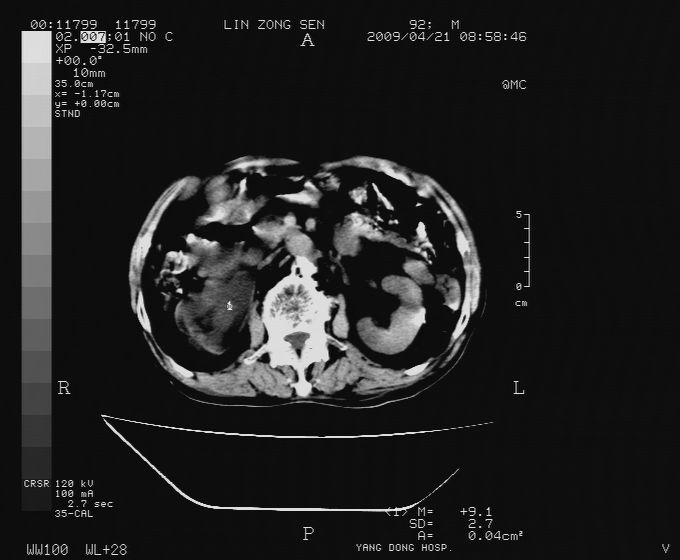

以下是引用卜一在2009-4-22 4:08:00的发言:[br]右肾积水伴输尿管上段积水!左侧肾多发囊肿!左侧腹壁软组织增厚,层次模糊,内密度较高—不排除血管瘤伴出血!